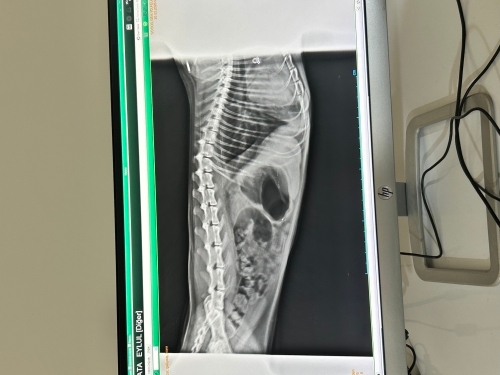

Kedim dünden beri abdominal solunuma başladı. Doktor röntgen çekti, diyafram cizgisinin belli olmadığını, ciğerlerinde sıvı biriktipini midesinin gazla dolu oldugunu ve kalbinin de normalde böyle gözükmemesi gerektiğini söyledi. İyi bir tablo değilmiş. Doktordan gece döndük. Perişan haldeyim, kedim 4 yaşında dişi kısır scottish, geçen sene de pnömoni olmuştu. O zaman veterıner de kalmıştı tam 10 gün. Şuan başka sehirdeyiz, burada genelde baytar var büykbaşla ilgleniyorlar. Pek kedi köpekle alakalı bilgileri yok sanırm. Doktor antibiyotik iğne, parazit hapı, bir kaç iğne daha yaptı. Hepsi birden ağır gelmezmi dedim ? Sağlıklı bi yanıt alamadım. Araştırdıgımda sıvının cekilmesi gerektiği ve önceliğin solunuma verilmesi gerektiğini öğrendim. Ama biz suan önceliği kabızına ve gazına vermiş olduk. Napacagız yarın sabah tekrar gideceğim. Kedime bir şey olmasını istemiyorum. Umut dolu gözlerle iyileşecekmi diye sordum. Ama yine güzel bi cevap alamadım. Napmam gerekiyor ?

Merhaba. Kediniz İçin Acil Durum Önerileri. Röntgen bulguları (diyafram çizgisinin kaybolması ve sıvı birikimi), hayati bir tehlikeye işaret ediyor.

Kalp Kontrolü (Eko): "Scottish kedilerde kalp hastalığı (GKM/HCM) riski yüksektir. Bu sıvı kalp kaynaklı olabilir mi? Furosemid (ödem attırıcı) yapılması gerekir mi?"